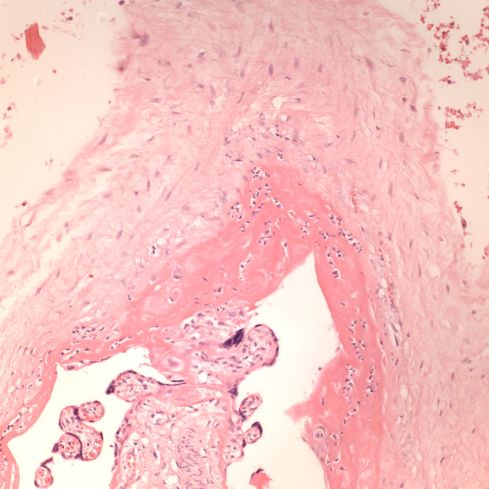

Figure 3: The villous stem vessels of the placenta on the right demonstrate endothelial ingrowth, but the villi on the left are not sclerotic. (20x H&E)